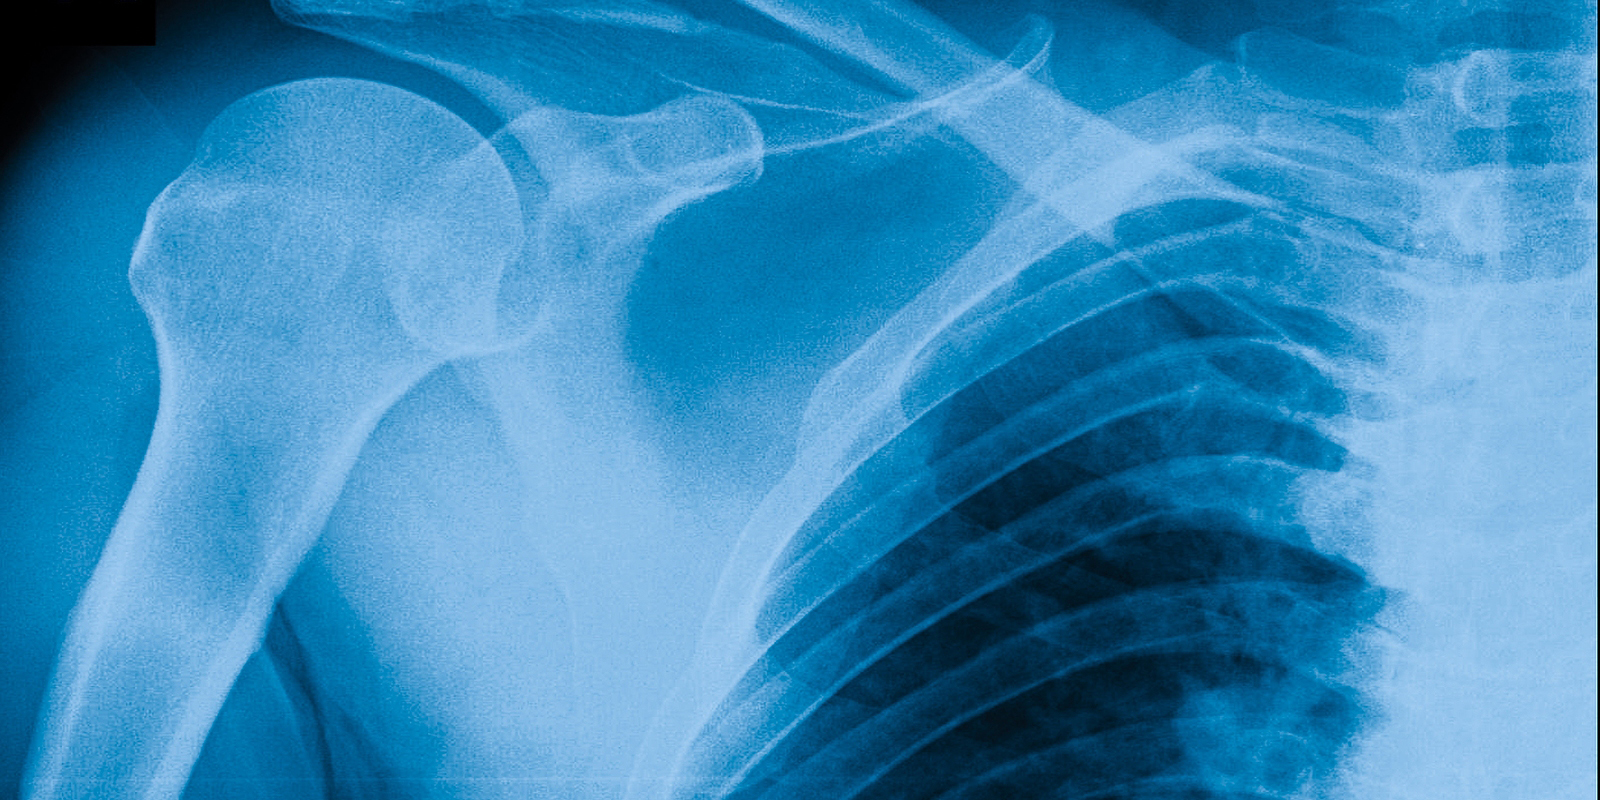

Рентген плеча: примеры снимков и их расшифровка

:background_color(FFFFFF):format(jpeg)/images/library/10853/IMG-0020-00001.jpg)